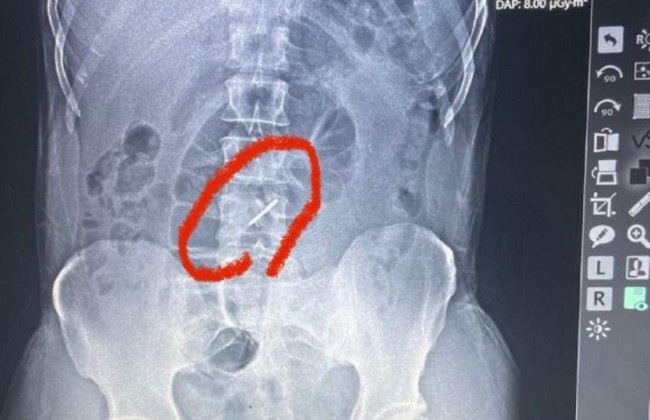

Під час одного з обстрілів «стрілка» від касетного боєприпасу зламала чоловікові два поперекові хребці та застрягла у хребті. Однак боєць (ім'я якого не називають з метою безпеки) не помітив цього. До шпиталю він звернувся лише тоді, коли біль у попереку почав справді йому заважати, а температура піднялася до 39 градусів. Медикам чоловік сказав, що в нього, мабуть, радикуліт.

За словами лікаря військово-польового шпиталю, львівського судинного хірурга Тараса Кобзи, військового відправили на рентген, після чого й з'ясувалась причина його болю у попереку.

«Під час обстрілу елемент касетної бомби потрапив у ліве підребер'я, зламав два хребці в поперековому відділі та застряг у хребті», — пояснив лікар.

«Боєць потрапив під обстріл ще 13 липня, а до нас звернувся лише на початку серпня. Він практично три тижні воював зі зламаним хребтом», – наголошує Кобза.